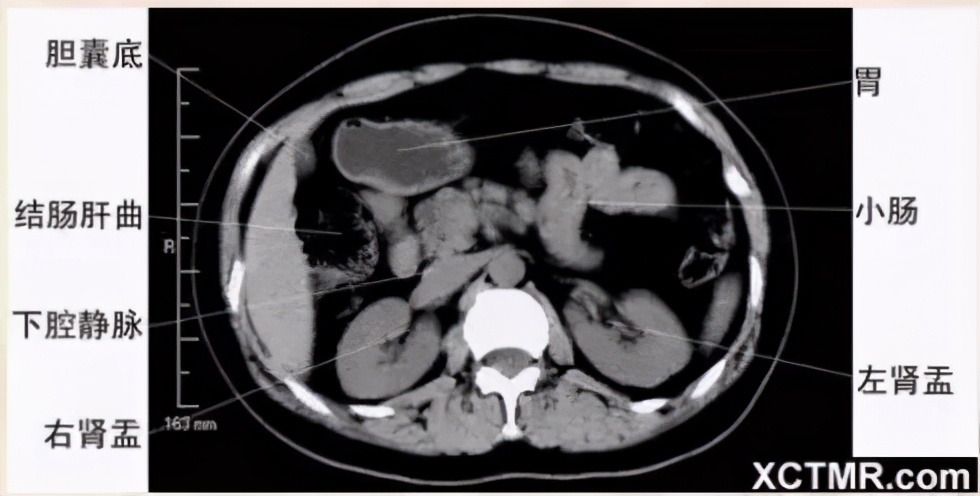

腹部CT